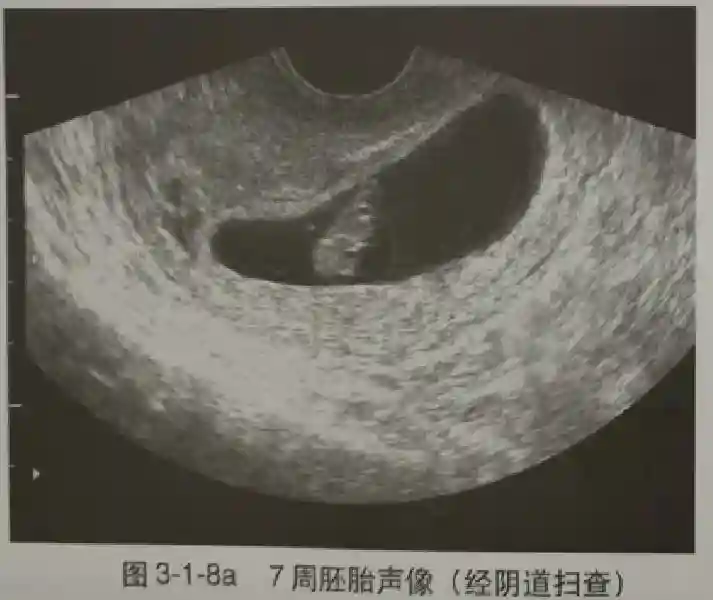

2️⃣卵黄囊:是妊娠囊内第一个解剖结构,直径<7mm。表现为小环状,中央为无回声,囊壁薄,内透声好。卵黄囊位于胚胎旁胚外体腔内。卵黄囊通常在孕5-6周时出现,5-10周稳步增长,一般不超过7mm,至12周消失。妊娠囊的大小与卵黄囊之间有一定关系,妊娠囊平均直径> 8 mm 时,经阴道超声均应显示卵黄囊,妊娠囊平均直径> 18 mm 时,经腹超声均应显示卵黄囊。

3️⃣胚胎:胚胎通常在6-7周时可以为超声显示,起初为胎芽,表现为卵黄囊一侧局部组织增厚,达到1 -2 mm 时才有可能为超声测量出来。达4-5mm时可见胎心搏动,相应孕周为6-6.5周,妊娠囊大小为13-18mm。胚芽长度≥7㎜时仍未见心管搏动,提示胚胎停止发育。胚胎的出现和妊娠囊直径的关系:妊娠囊直径> 16 mm 时,经阴道超声应显示胚胎。妊娠囊直径> 25 mm 时,经腹超声均应显示胚胎。

5️⃣羊膜:早孕期羊膜囊菲薄,超声常不能显示。孕7周以后加大增益或者用高频超声可以显示羊膜。羊膜囊位于绒毛膜内,胚胎位于羊膜囊内。随着胚胎增长,羊水增多,羊膜囊增大,孕12-16周时,羊膜与绒毛膜全部融合,胚外体腔消失。宫腔线一侧内膜内一圆形增强回声区,中央有小囊状液性暗区,宫腔线局部突起变形,称蜕膜内征,用于判断早早孕。#超声 #早孕检查 #妊娠